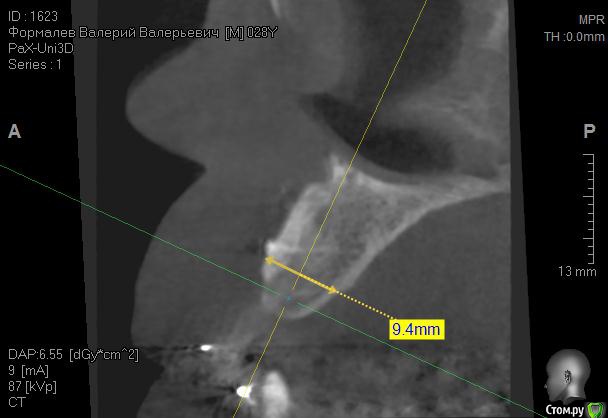

Kostoprav Опубликовано 8 июля, 2015 Поделиться Опубликовано 8 июля, 2015 ИЗНАЧАЛЬНАЯ СИТУАЦИЯ ПОЛУЧИЛОСЬ сори что нет фото до имплантации. Блок взял с тела челюсти, фиксировал двумя винтами (во время имплантации выкрутил только один), присыпал gen os, укрыл дермой-получил заметный прирост слизистой) имплант альфадент 3,75х11,5 2 Ссылка на комментарий

Kostoprav Опубликовано 8 июля, 2015 Автор Поделиться Опубликовано 8 июля, 2015 Видно что блок прирос. ЗдоровоОстальное оценить сложноМне нравится положение импланта в плане оси.Но уровень заглубления не ясенТакже не видно прироста десныВ общем мало данных для оценкиНо опять же вам именно она и нужна?по вестибюлярной поверхности заглубил приблизительно на 1мм с небной больше получилось. слизистая по сравнению с первым разом значительно толще стала, доказать к сожалению не могу так как не делал фото(: я выложил этот пост не только ради оценки, может кому из начинающих данный случай сгодиться 3 Ссылка на комментарий

Kostoprav Опубликовано 28 июля, 2015 Автор Поделиться Опубликовано 28 июля, 2015 Сколько времени прошло после фиксации блока? Чем забирает е блок? на момент имплантации 6 мес. забор блока делал линденманом Ссылка на комментарий